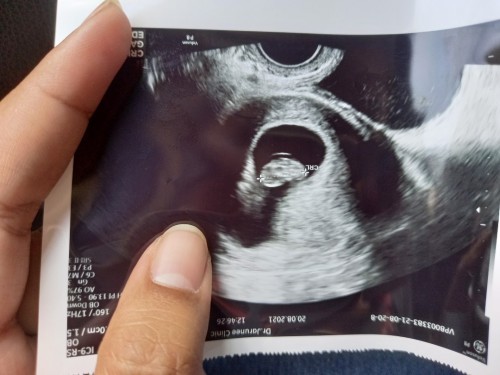

ตั้งท้องได้5สัปดาห์แล้วอันตราซาว2ครั้งยัฃไม่เจอเด็ก เป็นเพราะอะไรหลอค่ะ

อ่านเพิ่มเติมตอนตรวจ6weeksก็ไม่เจอตัวน้องเหมือนกันคะ แต่พอไปวันนี้ 8 weeks 6วัน ก็เจอตัวน้องและเห็นหัวใจเต้นตุ๊บๆๆด้วย ตอนแรกแอบกังวลว่าจะท้องลม คุณแม่รออีกหน่อยนะคะ

น้องยังเล็กอยู่ค่ะแม่ ไม่ต้องกังวลนะคะ บ้านนี้ไปหาคุณหมอตอน 5 วีค ซาวด์ผ่านช่องคลอดเจอแต่ถุงตั้งครรภ์ค่ะ มาเห็นตัวน้องตอนวีคที่7ค่ะ

น้องยังเล็กมากๆอยู่เลยค่ะ เคยซาวด์ครั้งแรกตอน7weekยังเป็นไข่กลมๆเล็กๆอยู่เลยค่ะ แต่ต้องซาวดฺทางช่องคลอดถึงจะเห็นค่ะ

น้องยังตัวเล็กมากๆ ค่ะ รอให้อายุครรภ์มากกว่านี้ก่อนค่ะ บ้านนี้ฝากครรภ์ครั้งแรก 6w ซาวด์ก็เจอแต่ถุงตั้งครรภ์ค่ะ